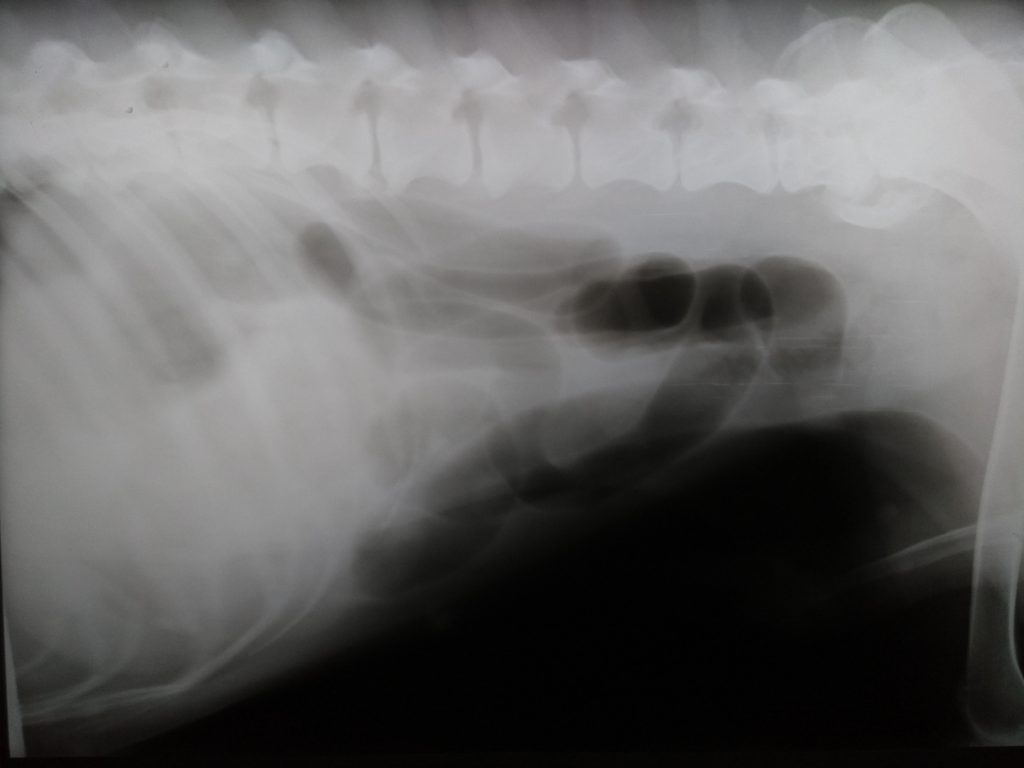

Se realiza estudio radiográfico de tórax y abdominal (no se incluyen todas las radiografías): El estudio no fue concluyente y el veterinario solicita estudio ecográfico abdominal a Dxia.

Radiografía lateral abdominal